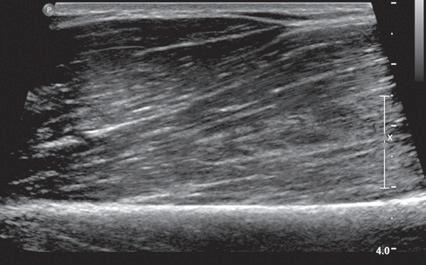

is fusion imaging, in which real-time ultrasound imaging can be superimposed on computed tomography (CT) or MRI; this has been used to assist with needle guidance for sacroiliac joint injections.17 One last technique is sonoelastography, which is used to assess the elastic properties of tissue. The three types of sonoelastography include compression elastography (using manual compression), shear wave elastography (using a directional shear wave), and transient elastography (using a short pulse).18 With compression elastography, manual compression of tissue produces strain or displacement within the tissue. Displacement is less when tissue is hard; it is displayed as blue on the ultrasound image, whereas soft tissue is displayed as red (Fig. 1.27). With regard to musculoskeletal applications, normal tendons appear as blue, whereas areas of tendinopathy, such as of the Achilles tendon or common extensor tendon of the elbow, appear as red.16,19-22 With shear wave and transient elastography, the velocity of the shear wave is measured to determine elasticity and has the advantage of less operator dependence and ability to produce qualitative and quantitative information.18,23

FIGURE 1.27 Ultrasound Elastography: Foreign Body Granuloma. Ultrasound image of common extensor tendon elbow shows suture granuloma (blue mass-like

Y. Morag, Ann Arbor,